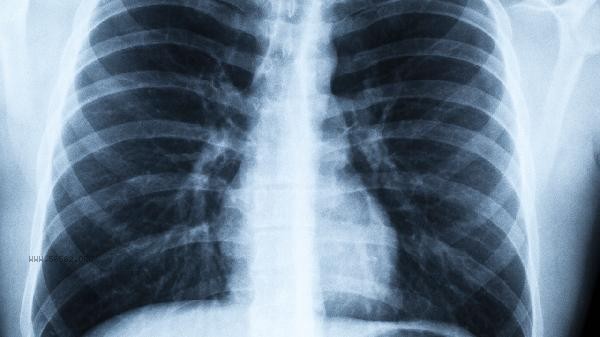

The most effective methods to increase lung capacity include abdominal breathing training, aerobic exercise, respiratory muscle training, smoking cessation and alcohol restriction, and improving body shape.